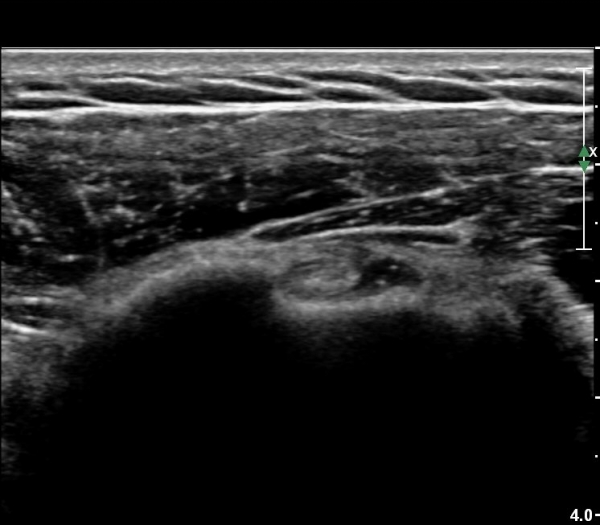

ŽÃËÀÚ¸¦ °ßºÀ ¿ÜÃø¿¡ ´ë°í ¾î±ú¸¦ ¿ÜÀüÇϸ鼭 °üÂûÇÏ´Ï ¿ÜÀü ½Ã °ßºÀ ¿ÜÃø¿¡ ¼ö¾×Àú·ù°¡

°üÂûµÇ¾î(»çÁø 10) ¿ÜÀü ½Ã °ßºÀÇÏ Ãæµ¹ÀÌ ÃßÁ¤µÈ´Ù.